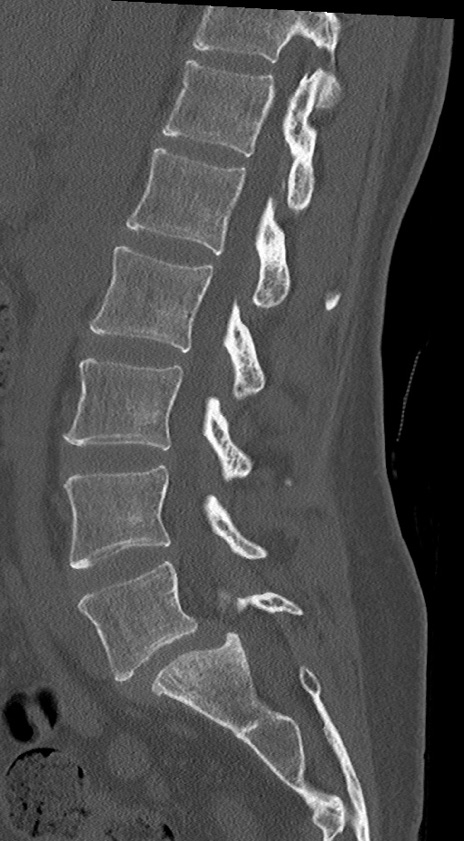

【整形】TIPS症例4 腰椎CT(矢状断像)

腰椎CT

T2WI(矢状断像)